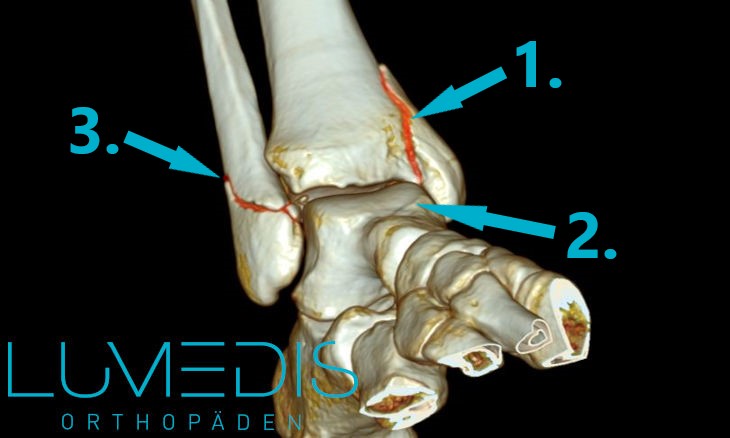

CT Rekonstruktion einer bimalleolären Fraktur des oberen Sprunggelenks

CT-Rekonstruktion einer Weber B-Fraktur